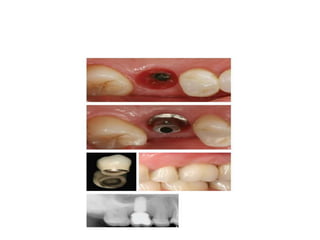

3.Impression techniques for

implant supported restorations

Healing abutment

Impression coping

Implant vs Implant analogue

Final abutments

Implant level impressions

Implant level impression

Pick-up (open tray)

Gingival mask

Closed tray (Transfer type)

Abutment level impression technque

Direct

Indirect